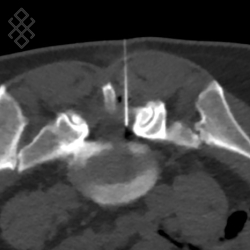

La durée de l'examen est d'environ 20 minutes. Le médecin radiologue fera un repérage de la région à infiltrer sous scanner. Ensuite, il effectuera une anesthésie locale pour introduire sous contrôle scanner une aiguille fine. Il contrôlera l'avancement de l'aiguille jusqu'au bon positionnement pour l'injection du corticoïde. Enfin, l'aiguille sera retirée et le soulagement pourra apparaître directement ou après deux jours.